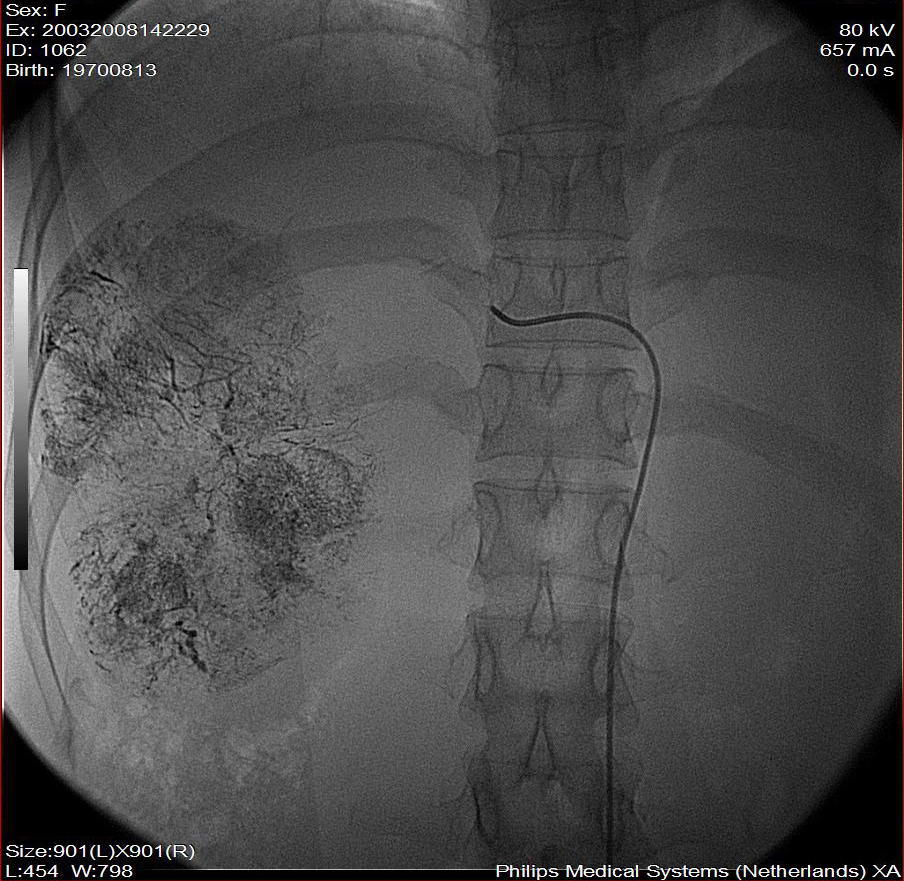

第二次(50天后)

栓塞的非常理想。

巨块型肝癌介入术后,肝左叶有转移吗(第二次进行肝左动脉栓塞了吗?)

好牛的,右肝动脉发自肠系膜上动脉,不用微导管分次进行末梢栓塞,肿瘤染色完整。再次学习了。